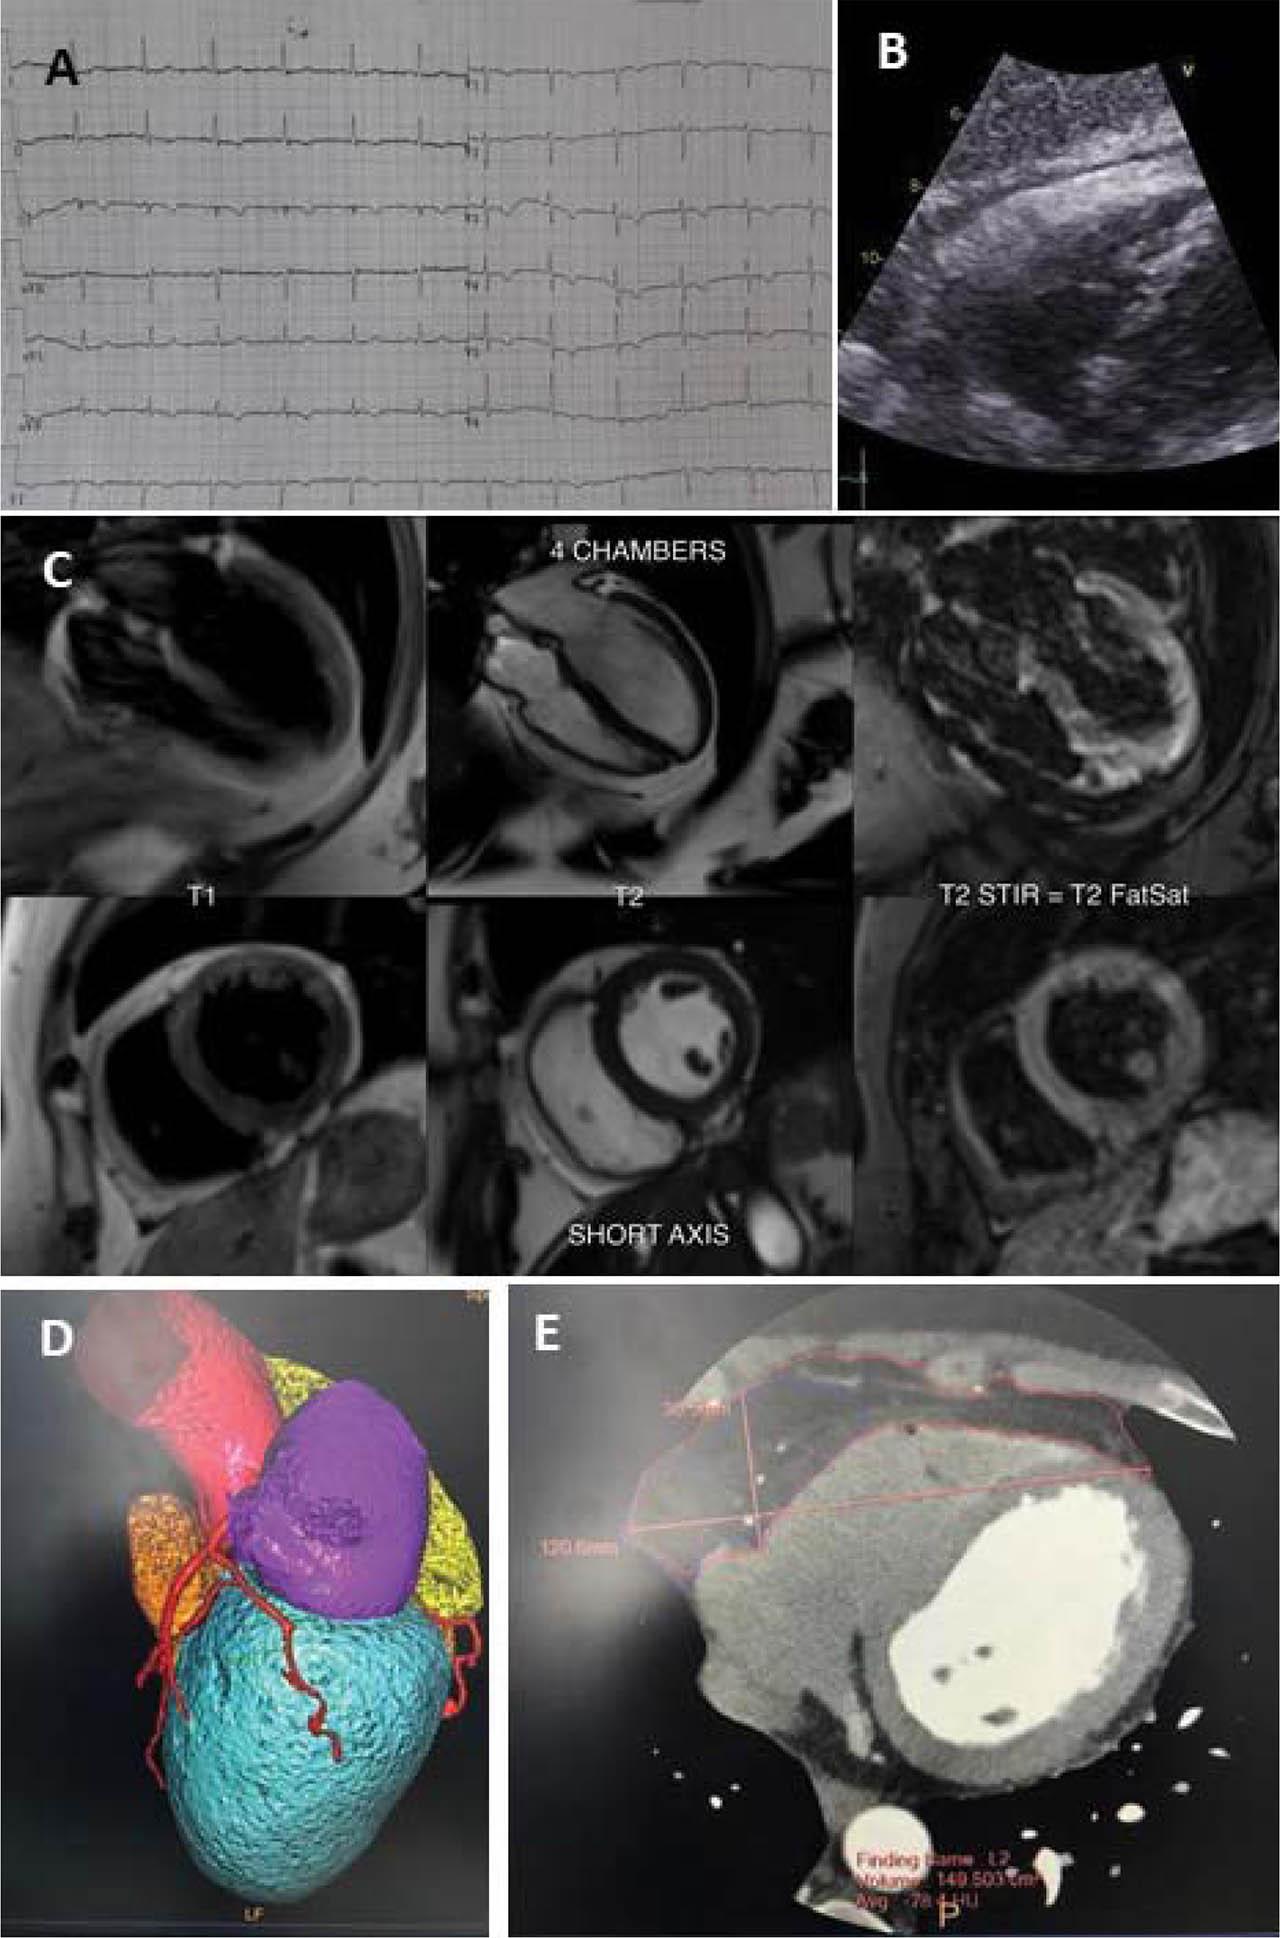

A 50-year old woman, with cardiovascular risk factors (CVRF) (smoking, hypertension), is referred to our cardiology department for atypical chest pain (rare episodes of persistent chest discomfort, not related to exercise) and for recently detected electrocardiographical (ECG) changes (diffuse negative T waves in V1–V6, DII, DIII) (Panel A). Of note, a resting ECG from 2015 showed a similar aspect.

After obtaining an unremarkable clinical examination and a similar ECG tracing, the 2D echocardiography revealed a normal sized left ventricle (LV) with preserved ejection fraction (LVEF) and normal segmentary systolic function. While examining the right ventricle (RV), the subcostal view suggested a hypertrophied RV free wall (measured as 10 mm, with apparent homogeneous echogenicity) (Panel B), with normal longitudinal function and no segmentary contraction abnormalities.

Cardiac magnetic resonance (CMR) was done with a referral suspicion of arrhythmogenic cardiomyopathy (AC). It found normal cardiac cavities, normal wall thickness of both ventricles (RV free wall of 3 mm), no late gadolinium enhancement, but described a large amount of fat with concentric disposition around the heart, maximum 9 mm anterior of RV and 3 mm posterior of LV (Panel C).

While this was not fully and safely explaining the ECG changes, and the patient presented with a low to intermediate pretest probability for coronary artery disease (CAD), an angio-computed tomography (CT) coronary scan was performed, with a calcium score of 7 AU, no significant coronary atherosclerosis and a hypoplastic circumflex artery (Panel D). No changes in pericardial thickness or structure were described, but a total volume of 149 ml of pericardial fat was measured (Panel E).

A. Electrocardiogram with inverted T waves in DII, DIII, V1–V6. B. Transthoracic echocardiography – subcostal view with impression of right ventricular hypertrophy. C. CMR image - four chamber view and short axis view - presence of pericardial fat tissue with high signal intensity on T1, T2-weight cine images and low signal intensity on T2 FatSat sequences. D. 3D reconstruction of coronary angio-CT with evidence of a hypoplastic circumflex artery. E. CT image with evaluation of pericardial fat volume.